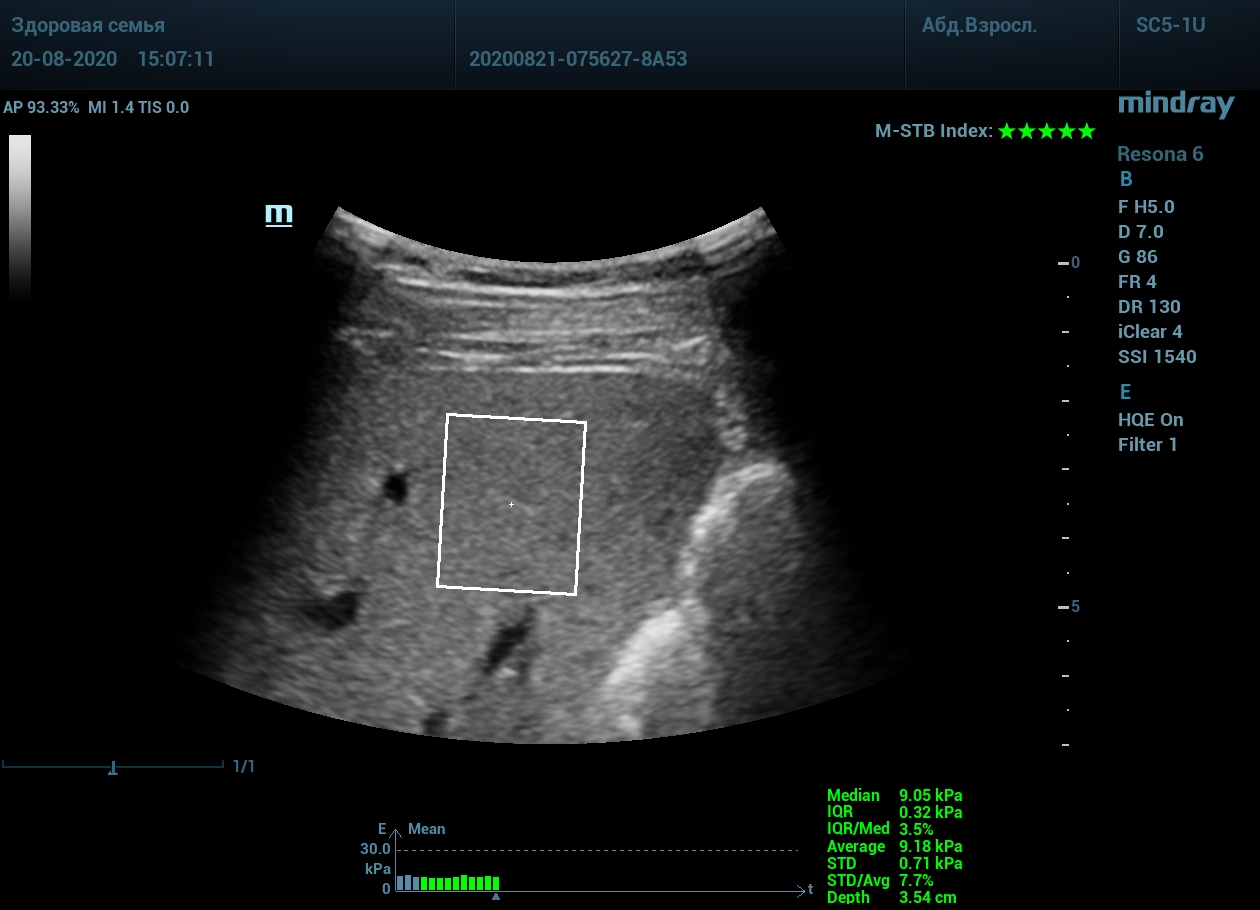

Как работает эластография сдвиговой волны? Датчик посылает плотный пучок ультразвуковых волн в ткани, ткани сжимаются, а затем возвращаются в исходное состояние за счет своей эластичности. Расправление ткани создают поперечные ультразвуковые волны, которые регистрируются трансдьюссером. Прибор во время исследования непрерывно отображает график значений плотности печени (kPa) в исследуемой зоне, достоверным считается график в виде прямой линии. Такая линия формируется путем получения близких по значению показателей. Количественным показателем является отношение межквартального интервала к медиане (IQR/Med). Допустимым считается результат с IQR/Med менее 30%. Чем данный показатель меньше, тем более точным является исследование. Для достоверного исследования в идеале нужно 10 значений.

- - Неподвижная печень. Достигается путем задержки дыхания на выдохе. Выдох позволяет уменьшить давление на печень органами грудной клетки и брюшной полости. Задержка дыхания останавливает её. Критерием качества является индекс M-STB, выраженным в количестве звезд. Прибор определяет его автоматически. 4-5 звезд индекса свидетельствует о неподвижной печени.

Для таких сложных случаев в приборах Mindray Resona предусмотрен режим HQ Elasto. В отличии от стандартной работы эластографии HQ Elasto позволяет собрать отдельное короткое измерение в сборный график. Достаточно задержки дыхания всего в пару секунд, показатель будет записан и добавлен в график измерений. Таким образом, короткими «залпами» ультразвуковых волн по печени доктор без проблем соберет все необходимые 10 значений и проведет автоматический анализ с расчетом медианы и IQR/Med.

Приводим видео пример: использованы 3 точки доступа печени, каждое значение графика получено прицельным выстрелом HQ Elasto и собрано в единый тренд. В результате анализа 10 значений получен удивительно точный результат - статистический разброс 3.5 % IQR/Med.